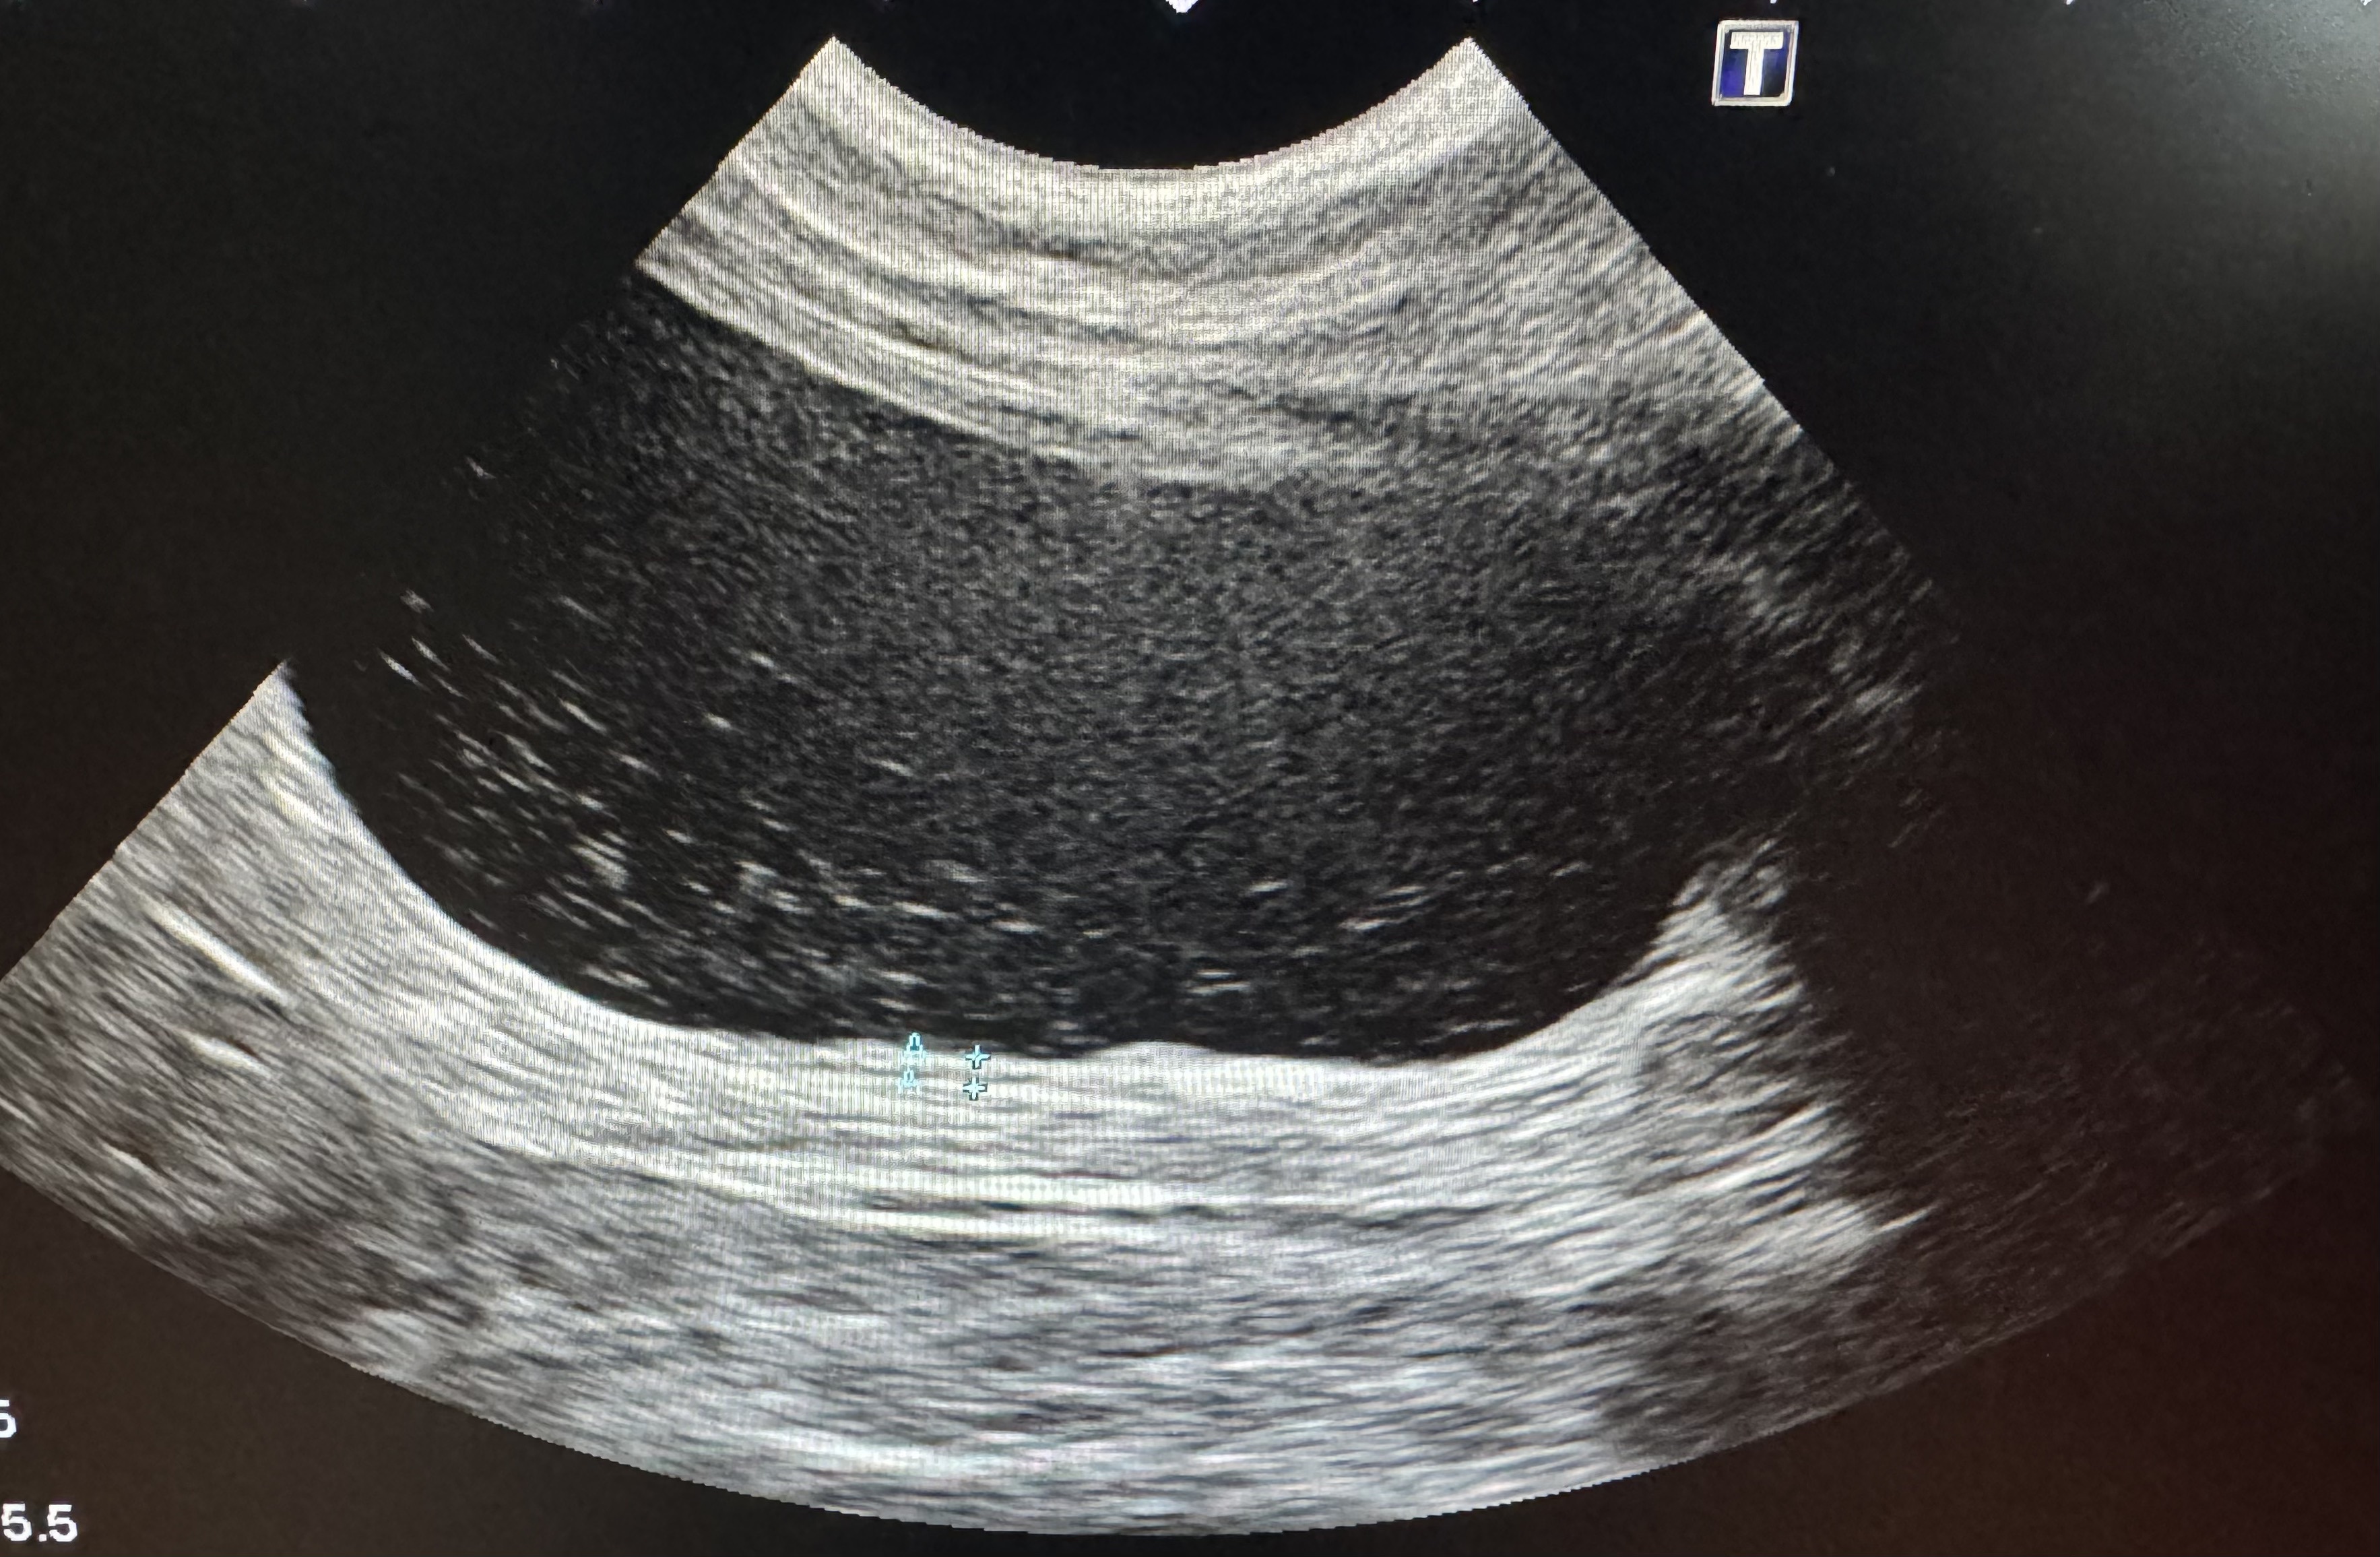

おしっこが出ないことを主訴に来院された2歳のオス猫の膀胱の超音波検査画像です。尿の貯留により明らかに膀胱が拡張しています。膀胱内も白の点がみえ、炎症産物や砂状の膀胱結石の存在が示唆されます。